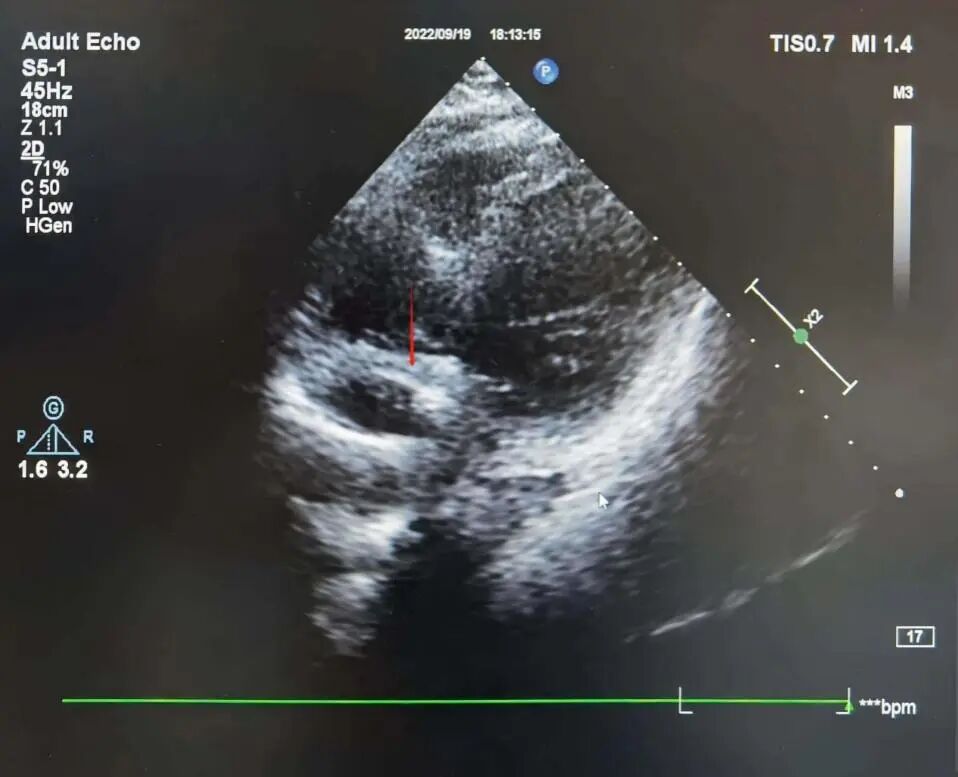

手术电极是什么意思超声引导,东莞市人民医院心内科团队“零射线”植入心系列双腔起搏器_https://www.jmylbn.com_新闻资讯_第5张

彩超下观察心房导线位置,呈“U”型挂于心耳